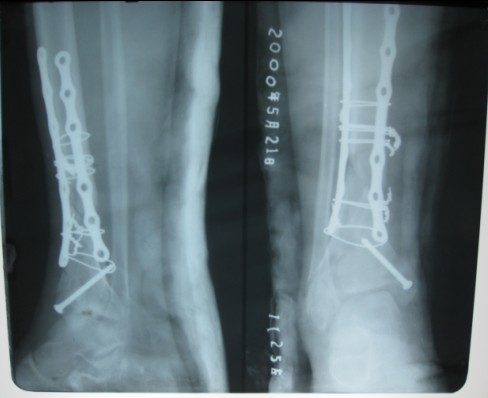

术后康复中

痊愈